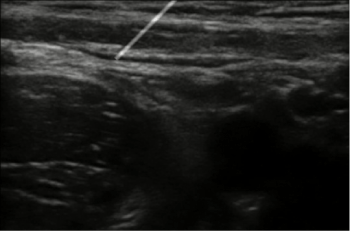

A working prototype of the concept has been built which is capable of producing synthetic ultrasound images based on real ultrasound images (Figure 13). The upper left corner window gives the color image captured by the Kinect along with the positions of the markers displayed. The lower left window displays the probe's center and needle's center positions. The lower right window shows the Kinect depth image. The top right corner window shows the visual simulation. This window shows ultrasound images generated based on the position of the probe on the dummy along with the virtual needle visualization. Images are generated in real time and changes in the position or orientation of probe or needle are immediately reflected in the updated images (figure 14).

The images generated by the simulation system closely match the real US images generated during scanning of the femoral nerve thus fulfilling the fidelity criteria. The images that are generated faithfully reflect changes in the position or orientation of needle or probe almost instantly, thus also meeting the latency criteria. We observed that the reproduced images in response to probe motion are very accurate. However, the needle visualization requires more refinement. It is quite challenging to get the needle in view, which could be beneficial for training purposes. It is our expectation that the needle visualization could be improved by adjusting the mechanical components of the system, such as stabilizing the markers on the block needle. Other stabilization algorithms such as the Kalman Filter [13] can be used to improve the needle visualization. When the position of the needle is controlled using a keyboard (during testing), very stable images like the one shown in Figure 13 are generated.